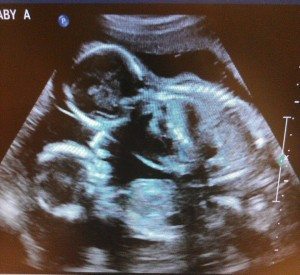

We found out our previous pregnancy wasn’t viable at our 8 week ultrasound. So going into this ultrasound (also at 8 weeks), so soon after, I was completely detached. And he was scared. So we got on the table and she started. She goes, “Ah, there’s the heartbeat. And here’s the other one.” And my husband just went, “The other what?” She replies, “Heartbeat.” And he still didn’t catch on. I turned my head and said, “There are 2 babies.” And then it went crazy from there. They are 15 months now.

I had an ultrasound at 11 weeks due to bleeding. I was told it was either a miscarriage or torn placenta. The tech said, “Here’s a heartbeat…and here’s the second heartbeat.” I admit it took me a second to catch on, but a full 10 minutes later my husband said, “Wait, are you saying there’s two babies??”

He almost broke my hand! He came with me to the scan and was holding my hand when straight away they said, “Oh yup, there’s one, there’s two, I’ll just check for a third!! We were both in shock!